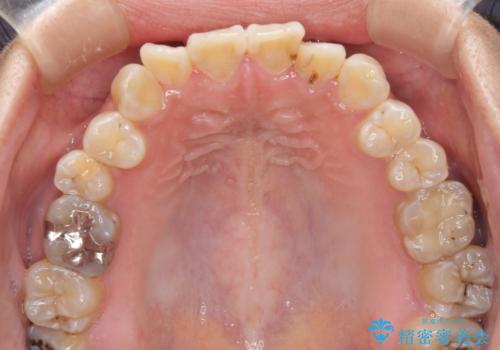

- 上下の前歯のでこぼこを気にして来院された患者様です。

職場の都合により、表側のワイヤー装置や着脱作業が頻繁なマウスピース矯正は困難とのことで、全く目立たない裏側矯正装置を用いて口元を整えることとしました。